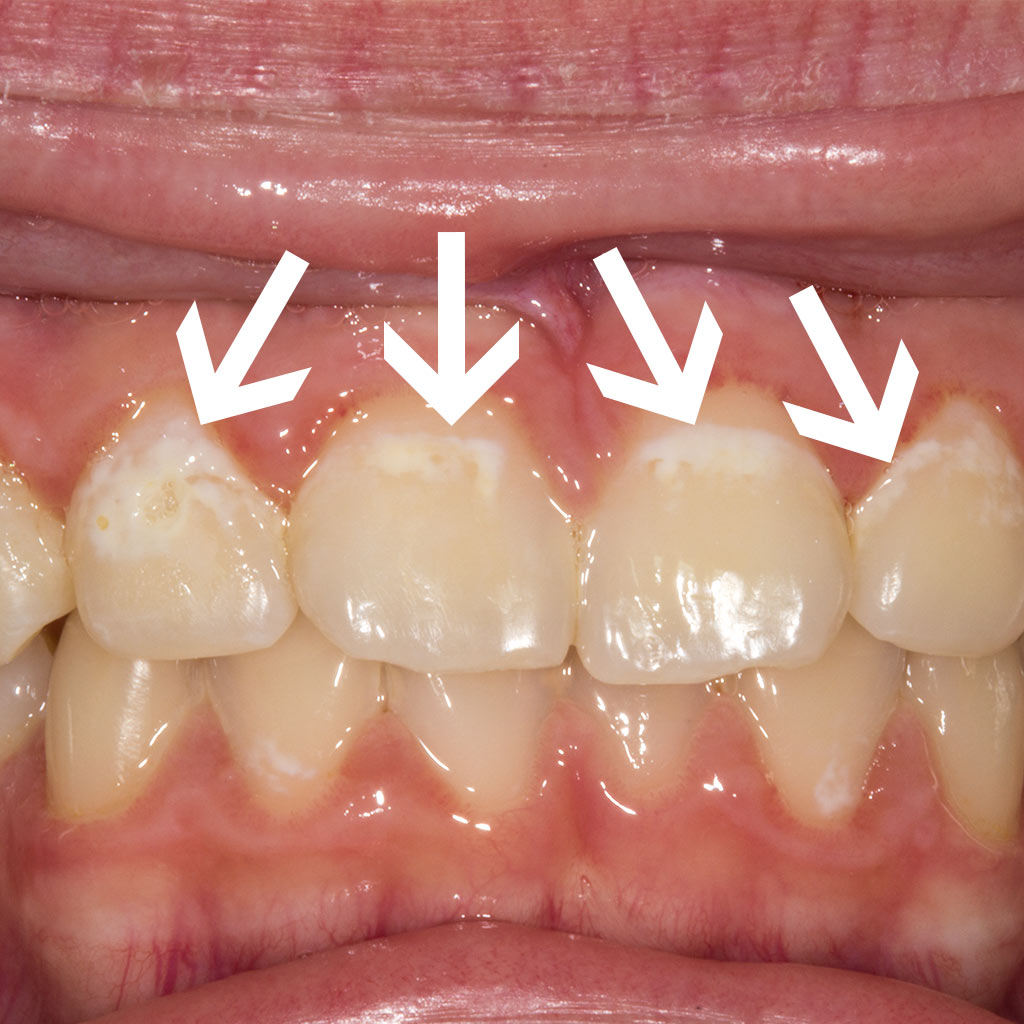

1. Кариес в стадии пятна - потеря естественного блеска, появление белых, светло-коричневых и темно-коричневых. Здесь есть два пути развития:

1)пятна вообще никак не изменяются долгие годы, обычно при должной гигиене и наблюдении.

2) на месте коричневого пятна образуется полость. Все происходит на этом этапе в поверхностных и подповерхностных слоях эмали практически бессимптомно.

2. Поверхностный кариес: на месте пятна образуется полость с нарушением целостности тканей. Возможны кратковременные реакции на сладкое, кислое, холодное. Кариес приближается к эмалево-дентинной границе.